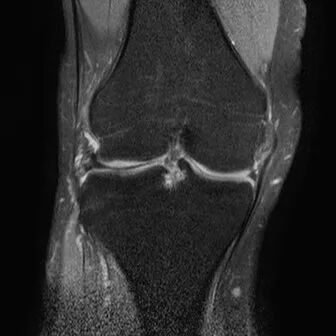

半月板桶柄状撕裂

1、多为纵形撕裂的特殊形式,有时来源于垂直(纵行)和水平撕裂2、多见于严重外伤的年轻患者3、内侧半月板发生率是外侧半月板的3倍

桶柄状撕裂MRI表现

1、宽度减小,在通过半月板体部的冠状面上蝶形消失,同时可见内移的半月板位于髁间窝、交叉韧带旁2、矢状面示残余的前角或后角变小或截断3、半月板前(后)角增宽或双半月板前(后)角征4、双前交叉韧带或双后交叉韧带征

桶柄状撕裂:宽度减小,在通过半月板体部的冠状面上蝶形消失,同时可见内移的半月板位于髁间窝、交叉韧带旁

桶柄状撕裂:半月板后角增宽